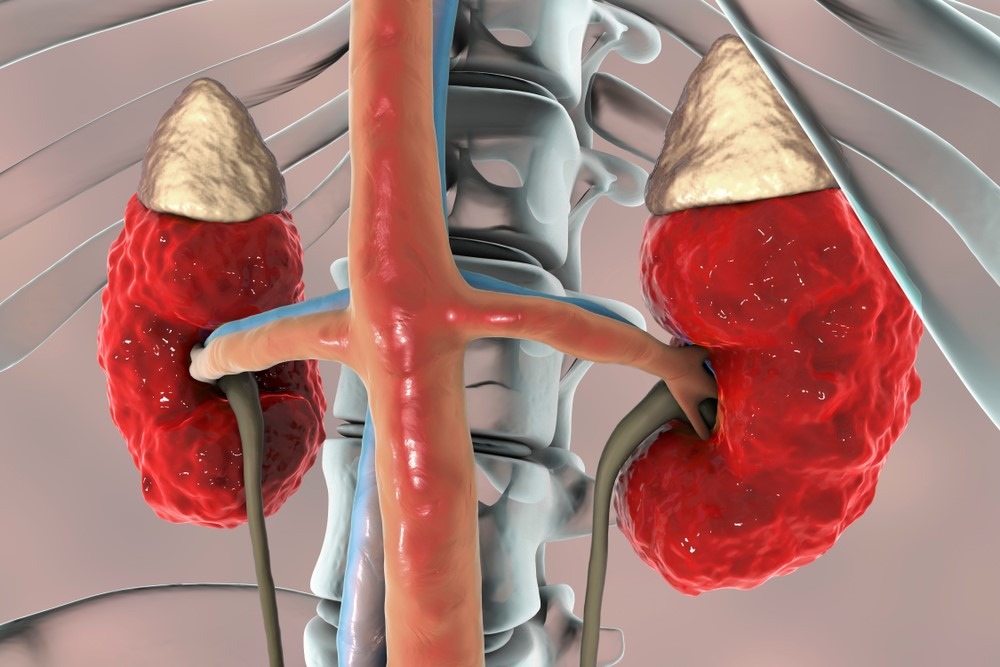

Thận giúp chúng ta loại bỏ các chất thải, chất thải chuyển hóa, urê và nước dư thừa ra khỏi cơ thể.

Khi thận bị suy, các chất thải không thể được đào thải và tích tụ quá mức, dẫn đến một loạt các triệu chứng “ngộ độc”.

Khi thận bị suy và ngừng hoạt động, chúng ta chỉ có thể dựa vào phương pháp thẩm phân máu để loại bỏ chất thải ra khỏi cơ thể hoặc ghép thận để thay thế quả thận không sử dụng và cho phép nó tiếp tục hoạt động.

Tại sao thận bị suy?

Thận của chúng ta đã suy yếu trước cả khi chúng ta già đi. Vì sao vậy?

(Ảnh minh họa: Internet)